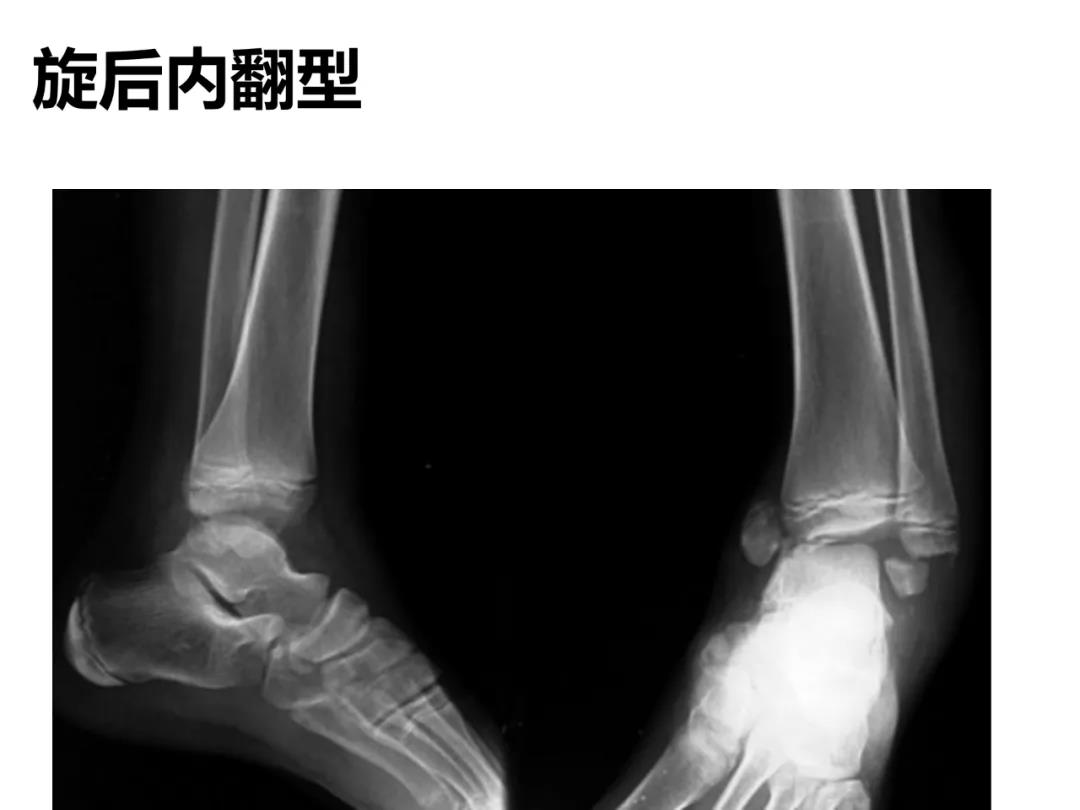

小儿骨科X线片汇总,临床读片宝典!